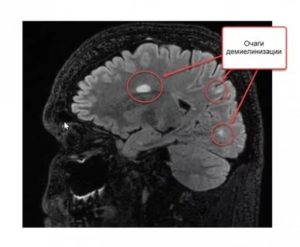

Очаги демиелинизации – это такие структурные образования в головном или спинном мозге, в которых отсутствует миелин, что приводит к нарушению передачи нервных импульсов и расстройству работы нервной системы в целом. Диаметр очагов существенно варьируется, может равняться несколько миллиметров или достигать нескольких сантиметров.

Псевдотуморозная демиелинизация проявляется общемозговой и очаговой церебральной симптоматикой. В 70% случаев сопровождается отеком мозгового вещества с повышением значений внутричерепного давления. Очаги демиелинизации обнаруживаются в белом веществе в ходе исследования МРТ головного мозга с использованием контрастного вещества.

На снимках отчетливо видны множественные кольцевидные очаги демиелинизации в белом веществе, чаще в лобных долях головного мозга, окруженные характерными участками ремиелинизации (восстановления нормального миелина). В большинстве случаев наступает летальный исход в течение нескольких недель или месяцев острого течения патологии. При ранней диагностике прогноз более благоприятный.

Основной метод инструментальной диагностики – нейровизуализация. Очаги демиелинизации, расположенные в головном мозге, преимущественно выявляются при помощи исследования МРТ, на снимках отчетливо видны участки пораженной ткани диаметром не меньше 3 мм. Очаги демиелинизации в структурах ПНС обнаруживаются в ходе электромиографии. Ангиография показывает степень повреждения сосудов.